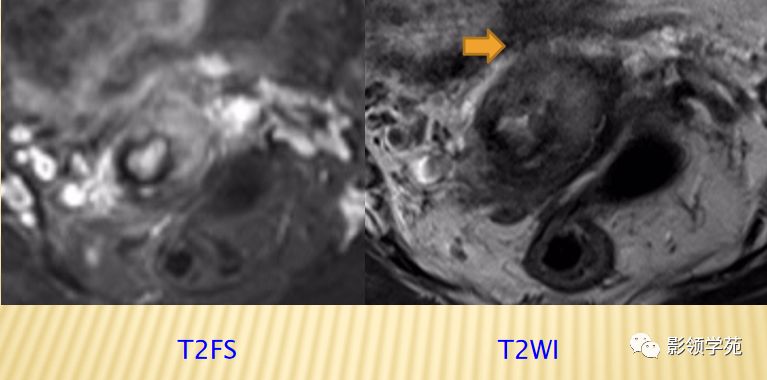

宫颈癌术后复发患者,DWI上病灶较T2 fs及T1+C更加明显